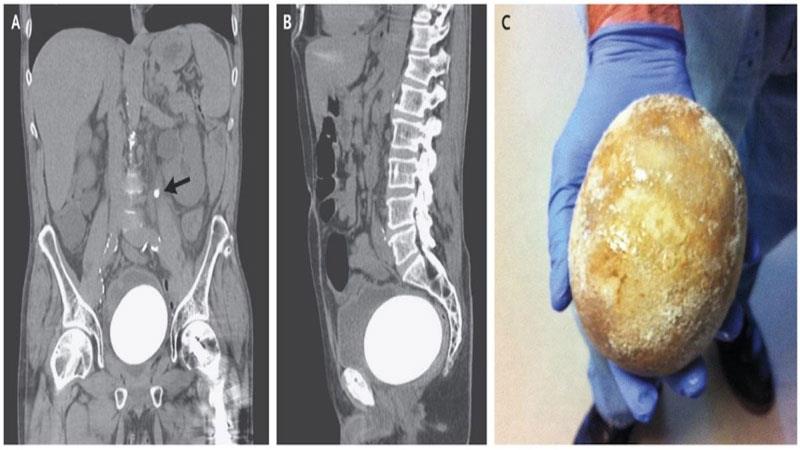

پزیشکەکان لە نەخۆشخانەی "پۆلاکۆڤۆ" سەرکەوتووبوون لە دەرهێنانی بەردێکی یەک کیلۆی لە میزەڵدانی پیاوێکی ڕوسی تەمەن 65 ساڵ.

نەخۆشەکە لەدۆخێکی زۆر خراپدا گەیەندراوەتە نەخۆشخانە کە نیشانەی سست بوونی گورچیلە و خوێن بەربوونی میزەڵدانی هەبووە،  پاش ئەوەی ڕەوانەی بەشی نەشتەرگەری کراوە پزیشکەکان زانیویانە ئەو بەردەی دروستبووە بەتەواوەتی ڕێڕەوی میزەڵدانی گرتووە بەڵام تیمەکە نەشتەرگەریەکی سەرکەوتویان بۆ ئەنجامداوە و پزیشکەکان پاش ئەمە نەشتەرگەریەکی دیکەی بۆ ئەنجام دەدەن بۆ ئەوەی توانای میزکردنی ئاسایی ببێتەوە.

پزیشکەکان ئاشکرایان کردووە دروستبوونی بەردێک بەم قەبارەیە هۆکارەکەی پەککەوتنی پرۆستاتە، هەروەها بەو هۆیەوە توانای میزکردنی نەخۆشەکە خراپ بووە و بەردێکی گەورە بەو قەبارەیە لەمیزەڵدانیدا دروستبووە.